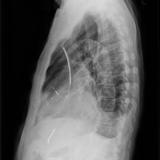

Cardiomegaly, esp RA Lat